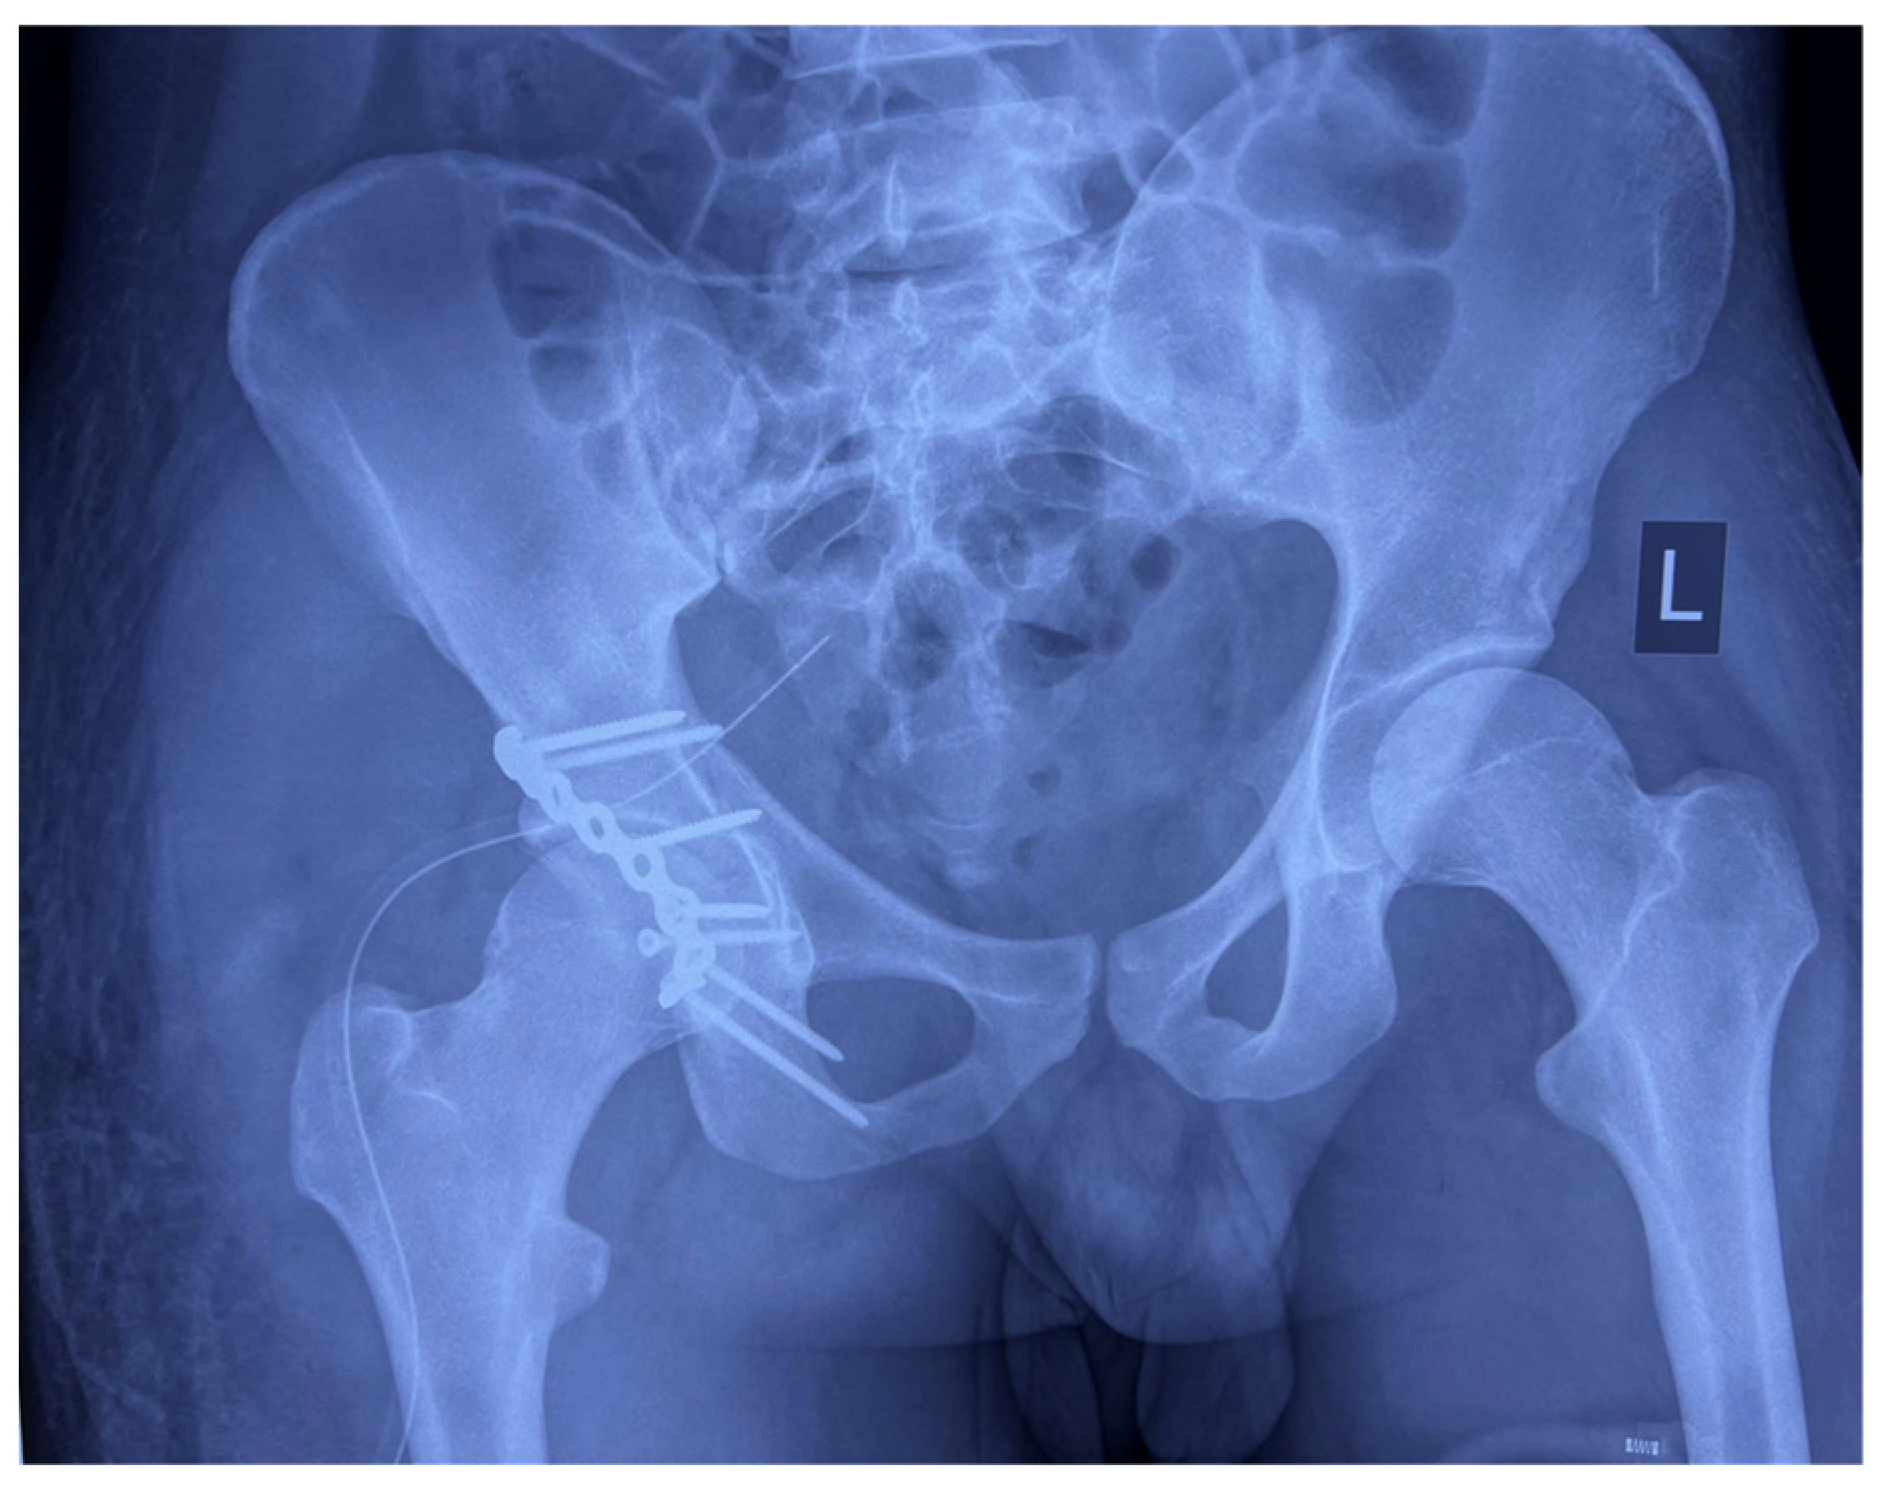

• Definitive management was performed three days post-injury via an open reduction and internal fixation (ORIF) of the right posterior acetabular wall using a Kocher–Langenbeck approach. Intraoperative findings included the following:

• Successful anatomic reduction and fixation achieved using a 3.5 mm reconstruction plate and cortical screws, restoring acetabular integrity.

Intraoperative radiographs as well as postoperative radiographs demonstrated anatomic reduction of the posterior wall fragment with proper positioning of the osteosynthetic material (Figure 4 and Figure 5). The postoperative neurovascular examination was completely normal, with no clinical signs of sciatic nerve injury.

Figure 4. Intraoperative Judet views—iliac oblique view, and obturator oblique view of the right hip—showing anatomic reduction of posterior wall fracture and proper positioning of osteosynthetic material.

Figure 5. Postoperative AP radiography of the pelvis showing anatomic reduction of posterior wall fracture and proper positioning of osteosynthetic material.